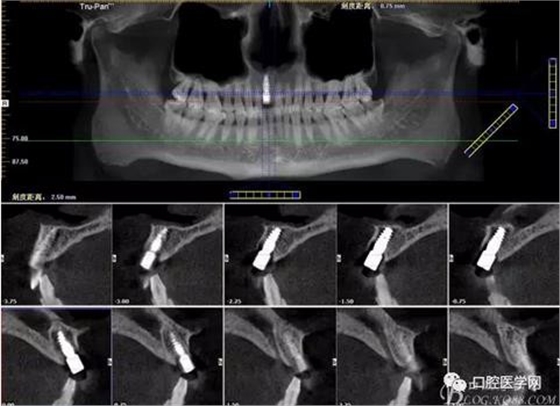

圖3 術后CT